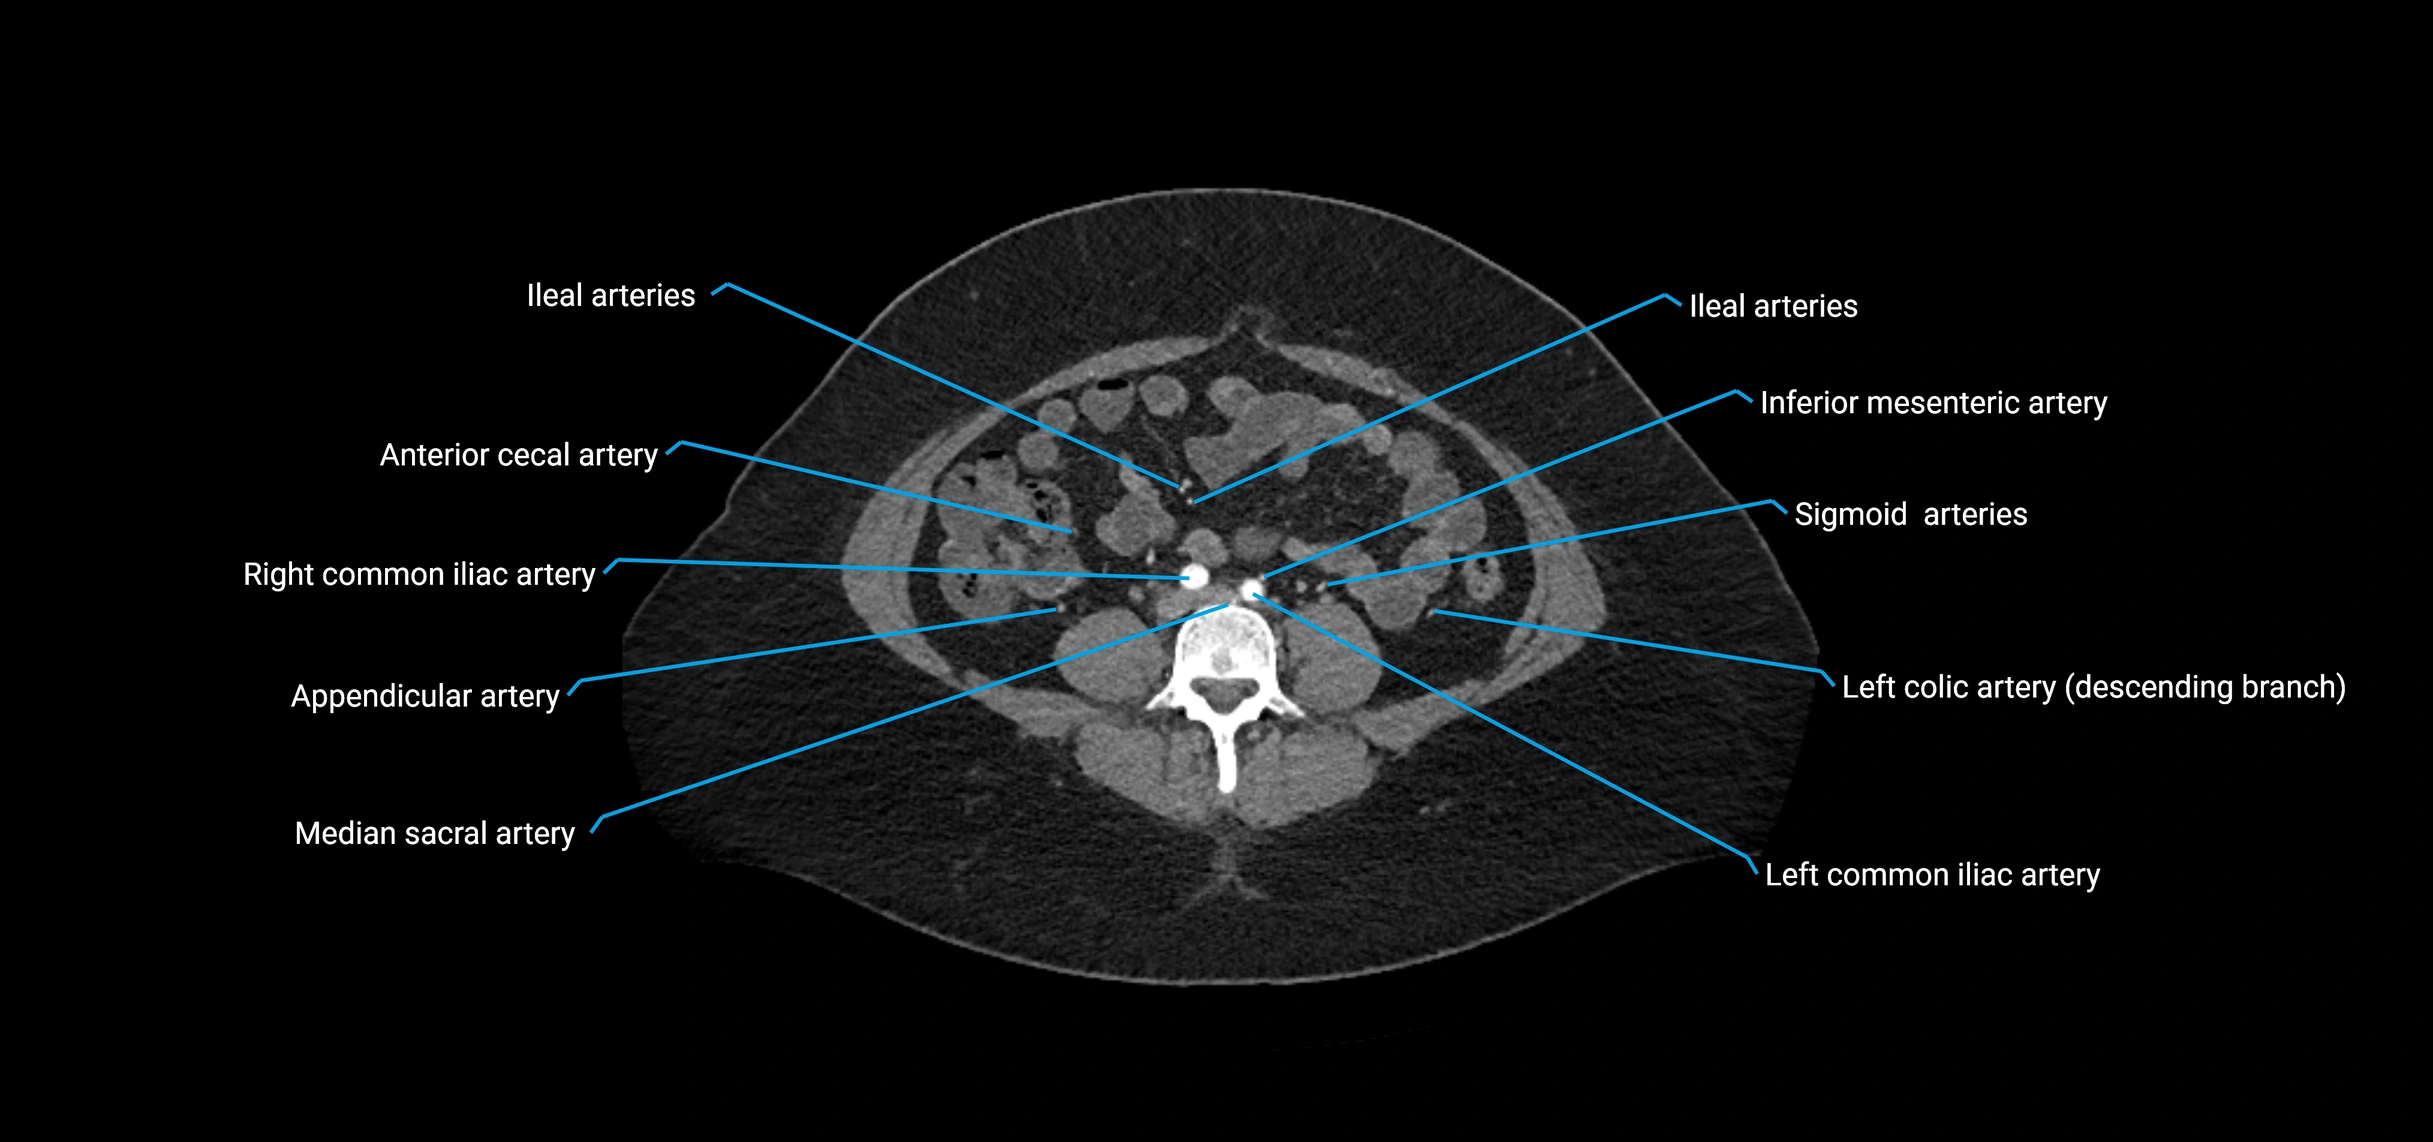

CT images

image

Contrast-enhanced CT (CTA):

• Gold standard for abdominal aortic imaging

• Provides excellent detail of lumen, wall, aneurysm, thrombus, and branch vessels

• Multiplanar and 3D reconstructions help in aneurysm measurement, stent graft planning, and dissection evaluation